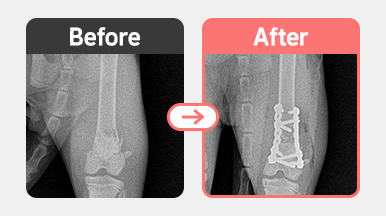

진단명 : 좌측 대퇴골 원위부 분쇄골절 (Distal femoral comminuted fracture)

진료내용 : 골절면 분괴 / Plate를 이용한 내고정술 진행

촉진 검사 및 방사선 촬영 결과, 좌측 대퇴골 원위부의 분쇄골절(comminuted fracture)이 확인되었습니다.

골절 부위는 여러 개의 조각으로 분괴된 복합골절 형태로,

정확한 정복과 강력한 고정력이 필요한 상태였습니다.

이에 따라 Plate를 이용한 내고정술을 통해

각 골편을 정렬하고 고정하는 방식으로 수술이 진행되었습니다.

1살 코숏 고양이 좌측 대퇴골 원위부 분쇄골절 수술 전후 방사선 사진, Plate를 이용한 내고정술로 골편 정렬 및 고정